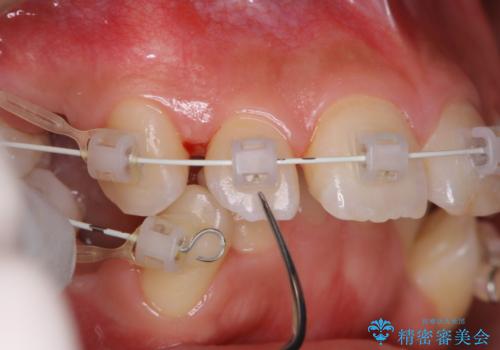

- これから矯正治療が開始される方です。装置の作成前にクリーニングを希望とのことでした。PMTC30分コースを行いました。

歯並が、がたついている場合はなおさら汚れが溜まりやすいです。矯正治療前や定期的にPMTCをすることで、矯正治療中の歯肉トラブルを防ぐことにつながります。